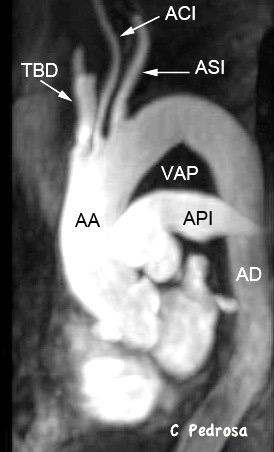

La línea de la arteria subclavia izquierda (ASI) es cóncava en el normal

ASI NORMAL

Frecuentes

Elongación de troncos

Aneurismas de ASI/ACI

Anomalías vasculares

Bocio/ Ca. de tiroides

Ganglios/ Grasa

Menos frecuentes

Tumores traqueales

Masas esofágicas

Tumor neurogénico

Tumores de Pancoast

Aneurisma de ASI

Aneurismas de TSA

74 pacientes

Degenerativos…63%

Iatrogénicos……24%

Trauma…………..8%

Genético………..3%

Micótico…………1%

ASD…50%. 2/3 lado dcho.

Carótida común 36%%

Carótida interna ..10%

TBD…………………..3%

Vertebral……………1%

Cury M et al.Supra-aortic vessels aneurysms: diagnosis andprompt intervention. J Vasc Surg. 2009